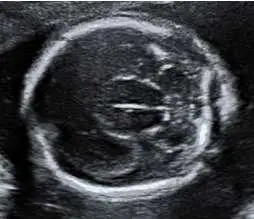

28 歲孕婦,G2P1 ,妊娠 16 週,接受超音波檢查如圖所示,下列何者為最可能的診斷?

前腦無裂畸形(holoprosencephaly, HPE)是胚胎前腦(prosencephalon)在妊娠第 3-4 週未能正常分裂為左右兩個大腦半球所導致的嚴重腦部發育異常。依嚴重程度分為三型:無葉型(alobar)、半葉型(semilobar)、有葉型(lobar)。產前超音波(尤其第二孕期)是主要篩查工具。

本題超音波影像為胎兒頭部橫切面(axial view),妊娠 16 週。影像所見:

- 單一大腦腔(monoventricle):可見顱腔內單一大型液體腔室,取代正常應有的左右兩側側腦室,此為前腦無裂畸形最具特徵性的超音波發現

- 中線結構缺失:正常大腦鐮(falx cerebri)及大腦縱裂(interhemispheric fissure)應在中線產生高回音反射(midline echo),本影像中此結構缺失或極不完整

- 視丘融合(fused thalami):中央可見融合的視丘位於腔室底部,此為 HPE 的另一重要診斷特徵

- 大腦皮質:可見薄層腦組織包繞於液體腔前方,分布不對稱

- 脈絡叢:可見少量脈絡叢組織,懸浮於單腔室中

上述影像高度符合前腦無裂畸形(無葉型或半葉型),核心特徵為「無法識別的正常雙側側腦室 + 缺失中線結構 + 視丘融合」。